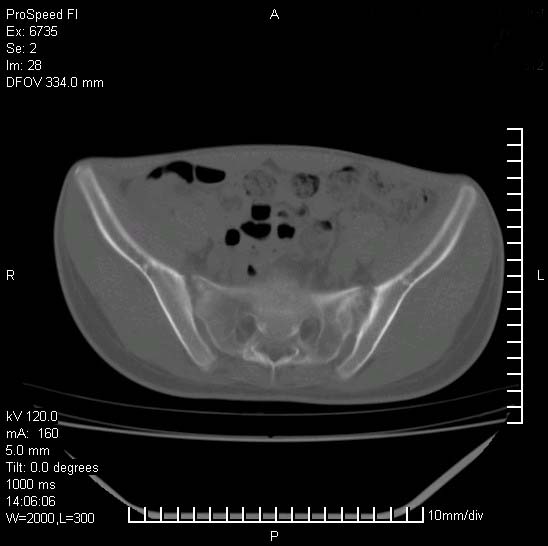

患者自诉胯部疼痛两年余,在当地服用中药,半月前至本院考虑骶髂关节结核,给予抗痨治疗。现发展至右下肢疼痛明显,活动受限,以膝关节处明显,拍膝关节平片无明显异常。

两侧骶骼关节改变,考虑强直性脊炎

左侧骶髂关节面限局性骨破坏,边缘硬化关节腔见钙化物;不出外tb

右侧骶髂关节也有类似改变,只是较左侧轻,首先考虑强直性脊柱炎,不除外结核,建议作hla-b27检查。

典型强脊炎改变,髋关节亦有累及

符合强直性脊柱炎表现。